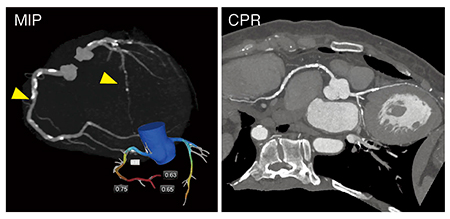

●症例4:心房中隔欠損症

40歳代,女性。Amplatzer閉鎖栓を用いたカテーテル治療の術前精査にCT検査が有用であるが,右房と左房の染め分けが必要なほか,VR画像の作成には均一な濃染が求められるなど,撮影はきわめて困難である。そこで,われわれは撮影の簡略化をめざし,70kVの4D撮影で多時相の3Dデータを得た上で,後処理にて必要な時相の画像を作成する“Time-blended”CTという手法を用いている(図4)。実際の画像(図5)では,16mL(370mgI製剤)の造影剤量で,サイズ計測のみならず,大動脈その他の立体的な解剖学的構造がきわめて良好に描出されている。

図4 “Time-blended”CTの概要

図5 症例4:心房中隔欠損症の“Time-blended”CTを用いた術前プランニング画像